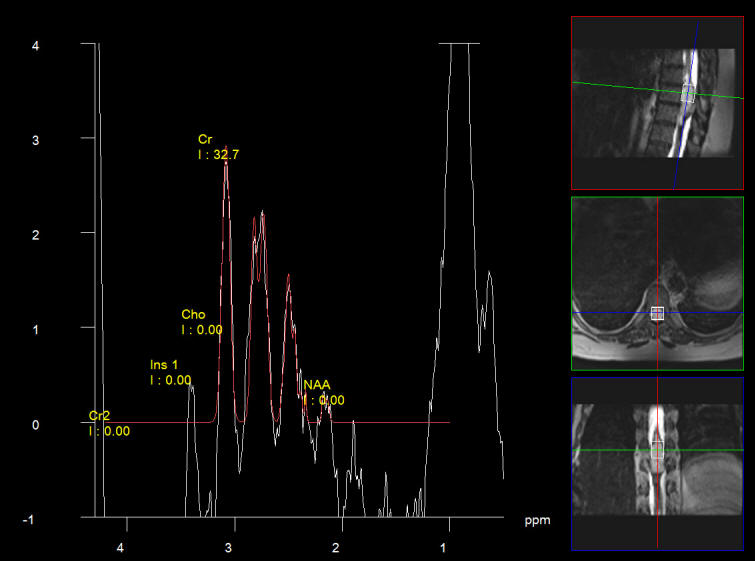

The patient was sent for MRI of the dorsal and lumbar spine. MRI lumbar done the same day showing huge cyst right kidney and bulge L3-4 and L4-5 disci. The dorsal spine showed intramedullary mass extending from D9 down to D10. Spectroscopy and DTI were performed and shown below.

Spectroscopy showing low NAA with low choline which is in favor for low grade ependymoma.